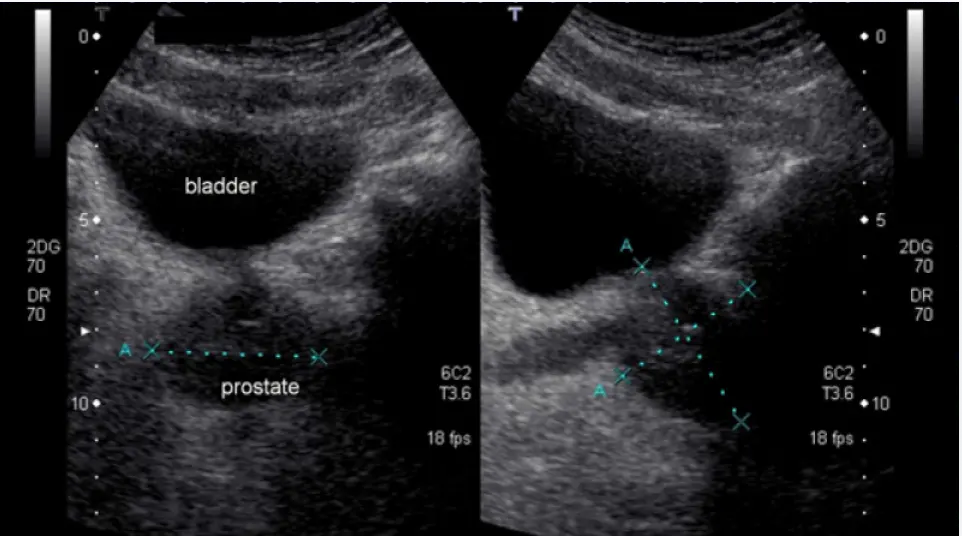

اولا ، التهاب البروستات لدي ليس مزمنًا. اصبت بالبرد أثناء الصيد ، في البداية اعتقدت أنني مصاب بالتهاب في المسالك البولية ، لأنني كثيرًا ما أجري. ثم كان هناك ألم في الفخذ ، وعدم الراحة أثناء التبول . باختصار ، ركضت إلى الطبيب ، قاموا بفحصي وجعلوني سعيدًا ، يقولون ، أنت ، يا صديقي ، مصاب بالتهاب البروستاتا. هنا ، بالطبع ، تومضت حياتي الجنسية بالكامل أمام عيني ، لقد ظننت انه لن استطيع ممارسة الجنس بعد هذا ، لكن الطبيب قال أننا سنتعالج.